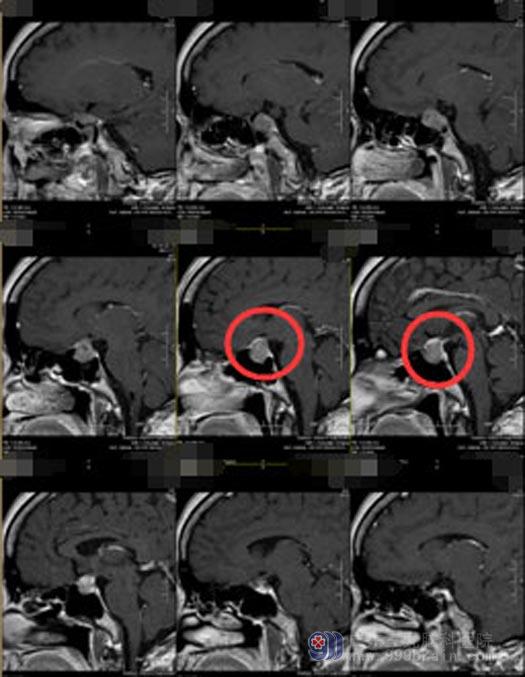

在广东三九脑科医院,赖女士的头颅MR检查结果提示:鞍内偏左侧-左侧海绵窦新增占位性病变,考虑垂体瘤复发伴卒中,病灶包绕左侧颈内动脉,压迫视交叉及左侧视神经颅内段。

征得赖女士及其家人同意后,医院副院长、神经外五科主任鲁明带领团队为患者行“内镜经鼻蝶鞍区复发侵袭垂体腺瘤切除术+颅底重建术”,手术过程顺利。